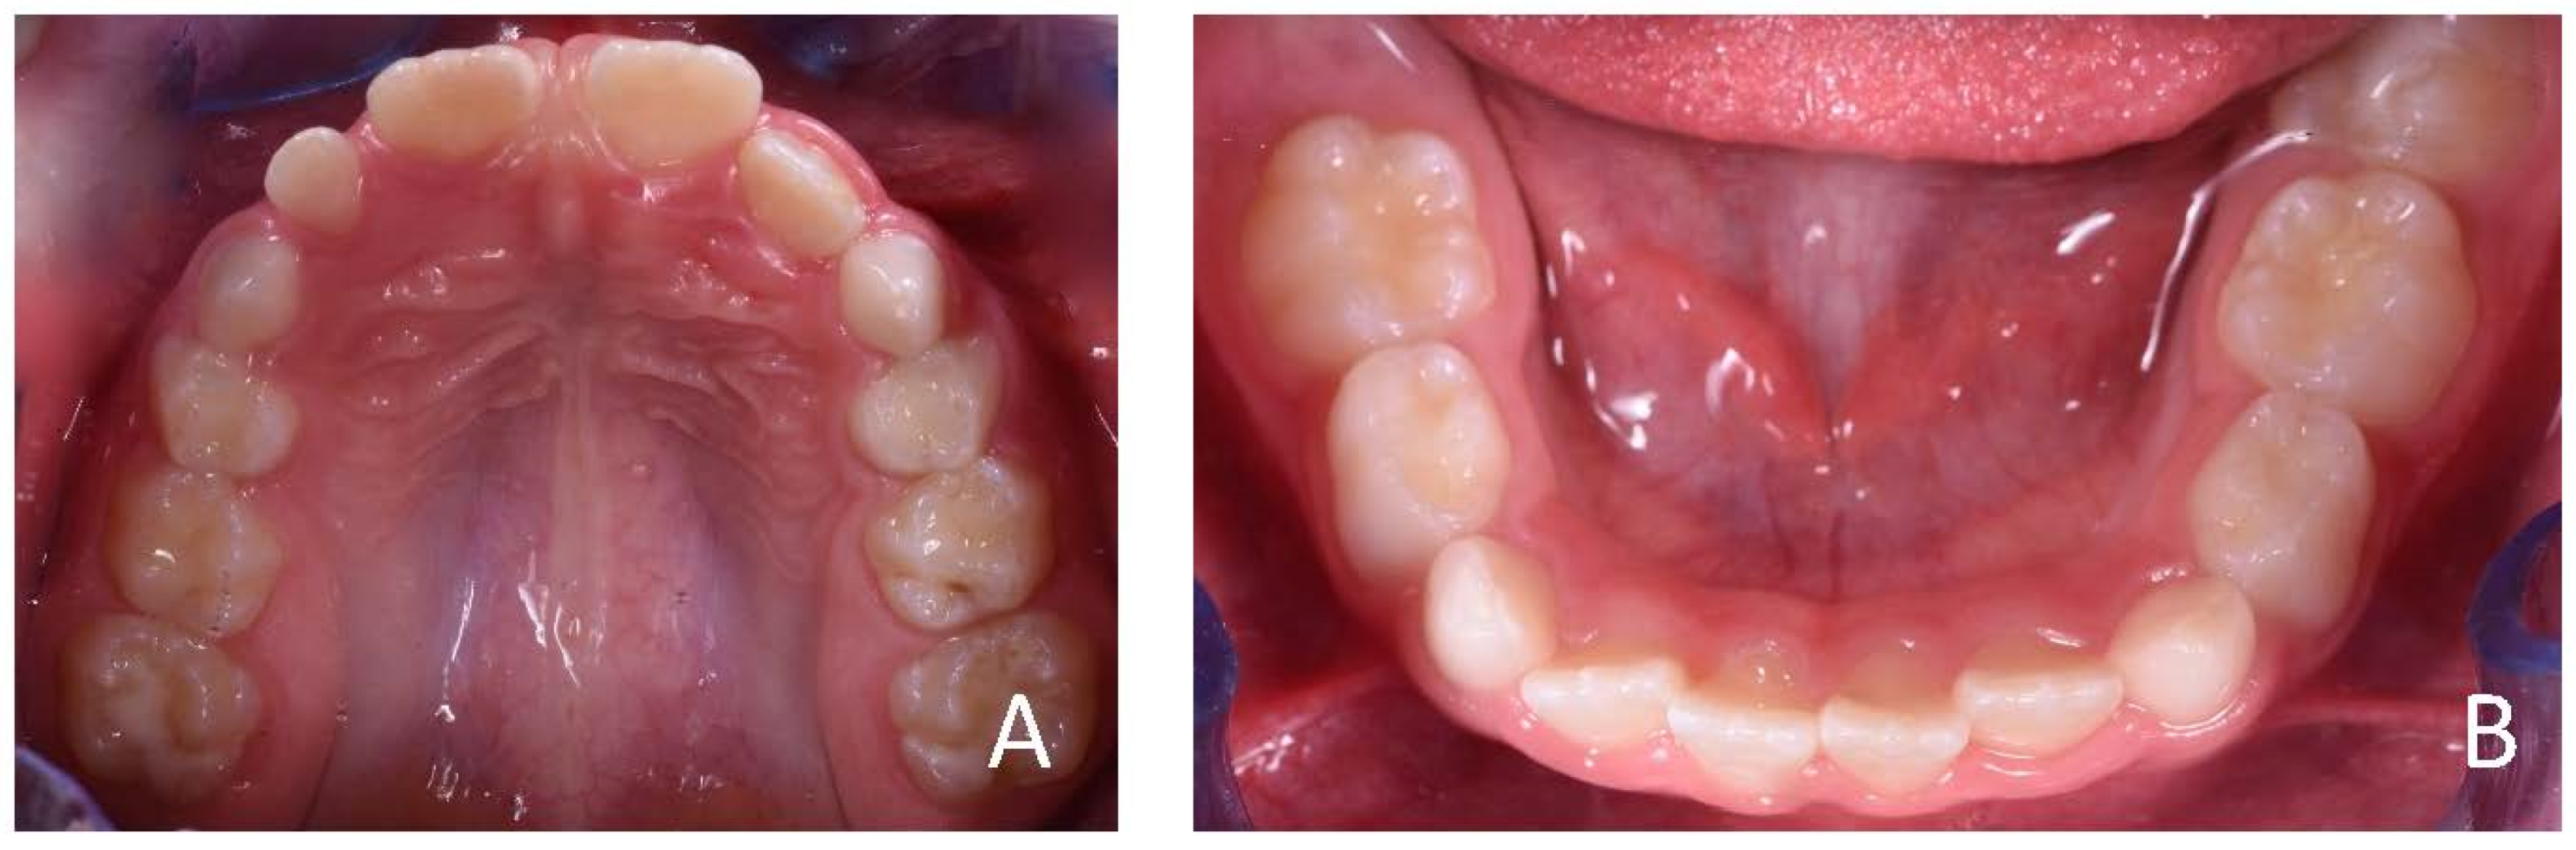

3.1. Clinical Case #1

3.2. Clinical Case #2

3.3. Clinical Case #3

3.4. Clinical Case #4